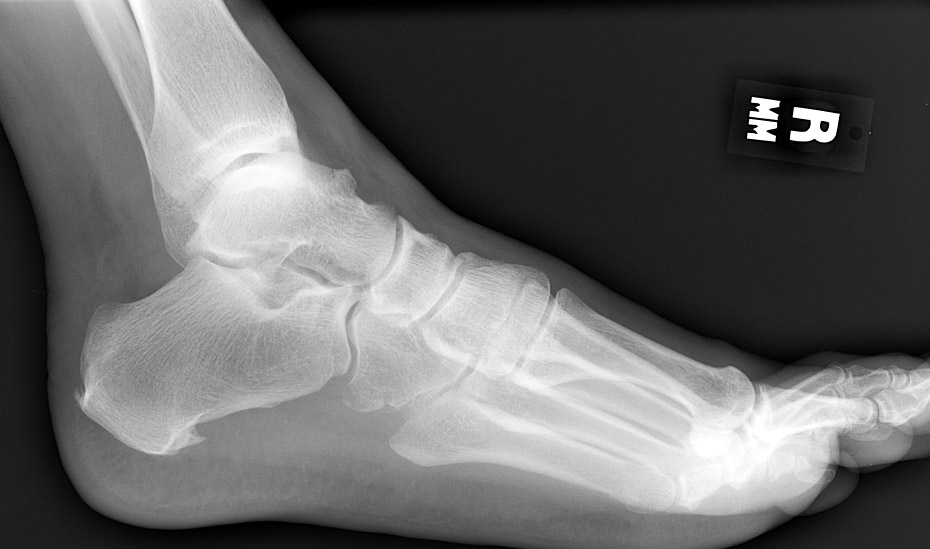

Return to Cuboid Fracture